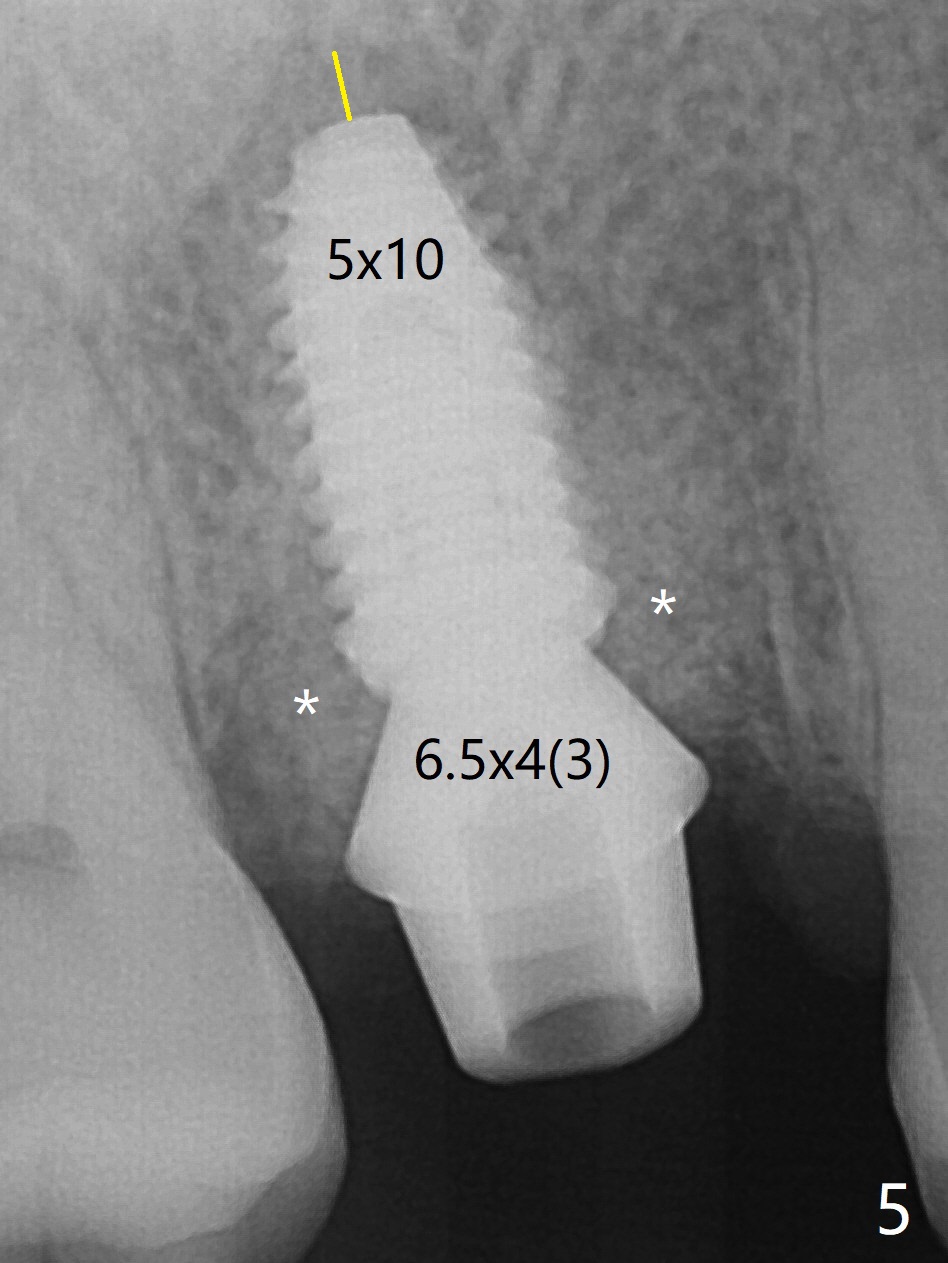

5x10

mm Immediate Implant

While the tooth #3 has a mesiodistal crack line, etiology may be due to chronic periodontitis with bruxism. After extraction, there is granulation tissue attached to the distobuccal (DB) root. The DB socket is larger than the mesiobuccal one (Fig.1). Osteotomy is initiated in the DB slope of the septum for 10 mm (Fig.2,3). Since there is ample apical bone, the depth of the osteotomy increases to 11.5 mm. When a 5x10 mm dummy implant is placed, primary stability is satisfactory (Fig.4 (yellow line: apical space)). The definitive implant remains the same dimension with deeper placement (Fig.5,6 (~ 20 Ncm)); with placement of a 6.5x4(3) mm abutment and Vanilla/Osteogen Graft (*), an immediate provisional is fabricated in place (without taking out for trimming) with sufficient clearance with the opposing dentition. It appears that the moderately long implant (10 mm) is able to achieve primary stability for immediate placement. When the provisional is removed 2 months postop, bone graft seems to be adhered to the socket (Fig.7). To improve local hygiene, the provisional does not return. The implant seems to have osteointegrated 3.5 months postop (Fig.8). The crown/abutment is loose approximately 1 year post cementation. Due to her daughter's contracting COVID 19, she postpones returning for approximately 1 year. The access hole is opened, crown/abutment (6.5x4(4) mm) removed, proximal contacts reduced, crown/abutment reseated without certainty. BW shows incomplete seating probably due to bony interference (Fig.9). A 5.5x4(4) mm can not be seated (bouncing, probably due to soft tissue interference). When a 4.5x5(4) mm abutment (UF) is seated, hand tightening is smooth, confirmed by BW (Fig.10). Two weeks later, the new crown is cemented intraorally. The crown/abutment is removed for cleaning. The abutment screw is torqued at 20 NCM.